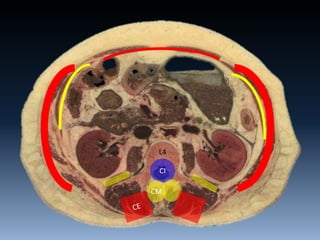

CI

L4

CM

Core

100 kg em L4/L5

(Bogduk et al., 1992)